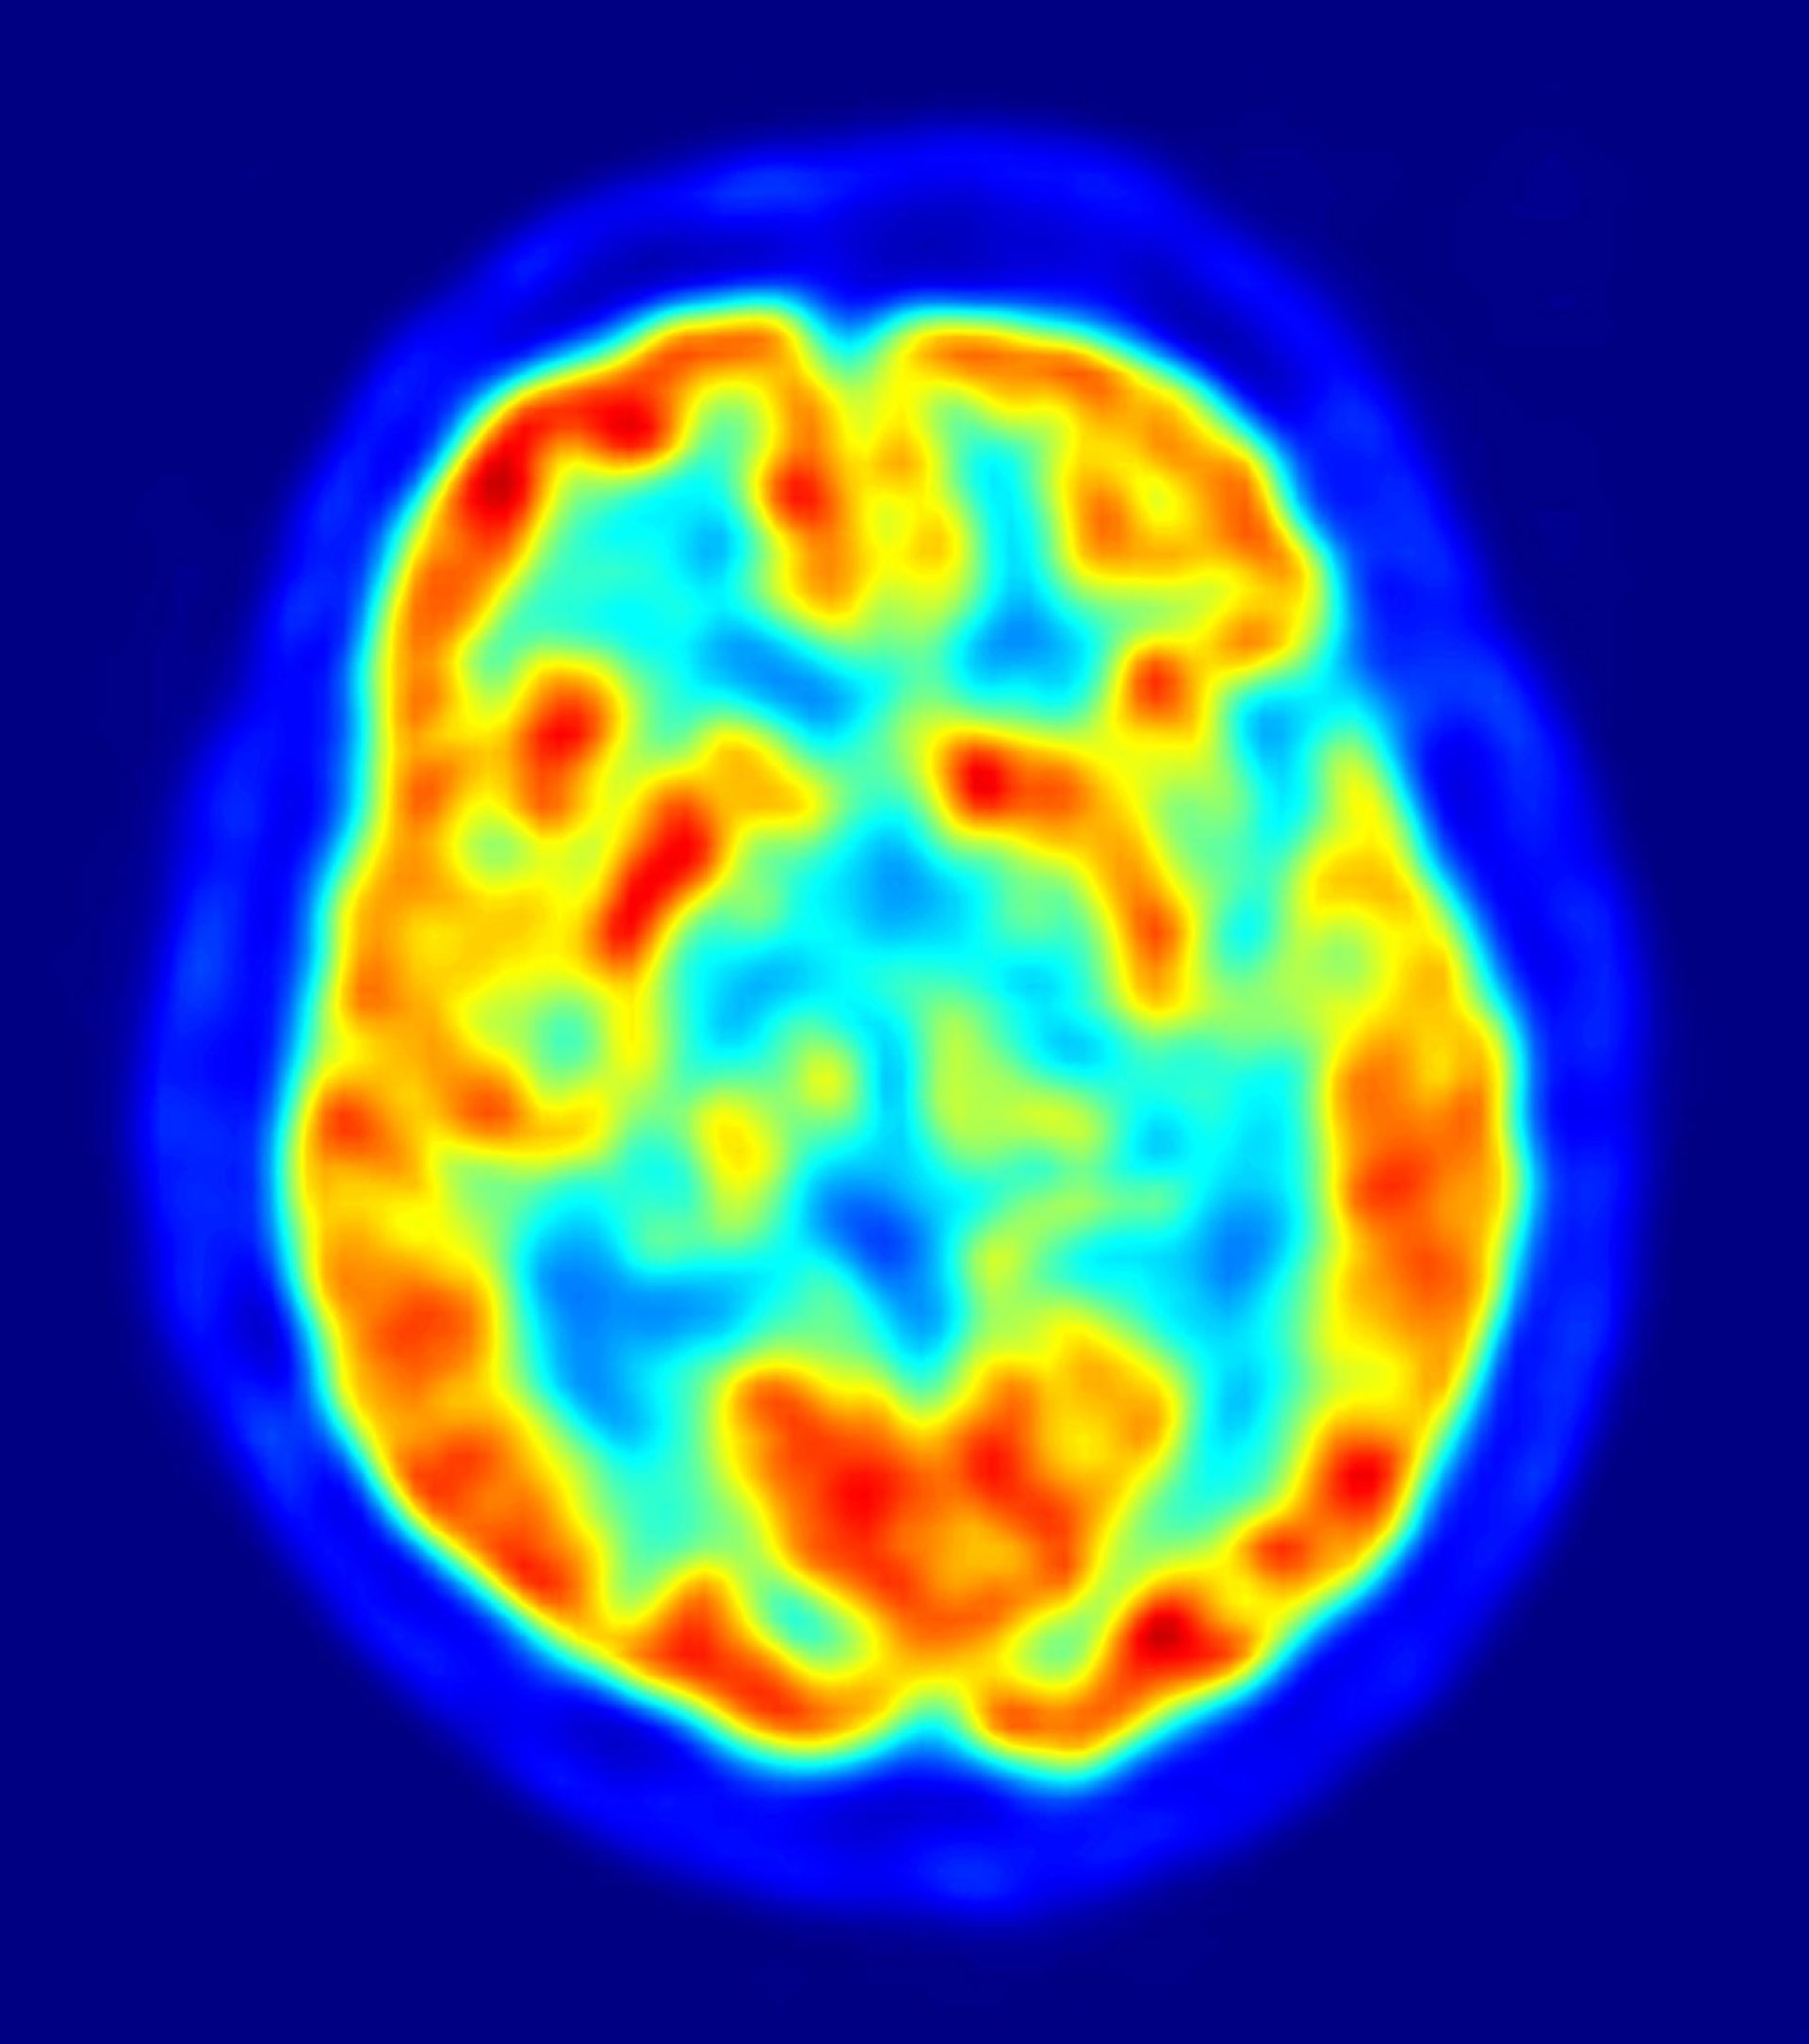

Un equipo de científicos ha descubierto una mutación, limitada al tejido cerebral, que causa hemimegalencefalia (HMG), una condición en la que una mitad del cerebro se agranda, y se vuelve disfuncional -causando discapacidad intelectual y epilepsia severa. La investigación, publicada en la revista 'Neuron', sirve de modelo potencial para otras enfermedades neuropsiquiátricas complejas, que también pueden ser causadas ??por mutaciones en el cerebro.

"La sorprendente asimetría del cerebro, en las personas con HMG, ya indicaba que esta enfermedad puede ser causada por una mutación espontánea restringida a la mitad del cerebro, y detectable por estudio directo del tejido cerebral afectado", explica la primera autora del estudio, la doctora Ann Poduri, del Hospital Infantil de Boston, y la Escuela Médica de Harvard, en EE.UU.

Los pacientes con HMG suelen sufrir decenas de ataques por día, lo cual perturba su desarrollo cognitivo, y lleva a los médicos a tomar la difícil decisión de eliminar tejido cerebral, en un intento desesperado por controlar las convulsiones. Afortunadamente, estas operaciones, con frecuencia, tienen éxito en el control de las crisis, y permiten que los niños afectados se desarrollen con normalidad. A partir del tejido cerebral proporcionado por estas operaciones. Poduri y sus colaboradores identificaron mutaciones en el gen AKT3 del tejido cerebral con HMG.

"Nuestros datos sugieren que las mutaciones espontáneas, resultantes de la activación anormal de AKT3, contribuyen al crecimiento excesivo de la mitad del cerebro. El tamaño y la arquitectura de HMG pueden ser determinados, en parte, por la etapa en que la mutación se produce, en relación con la etapa de desarrollo del cerebro ", concluye el coautor del estudio, el doctor Christopher Walsh, del Hospital Infantil de Boston, el Instituto Médico Howard Hughes, y la Escuela de Medicina de Harvard. Walsh añade que, "esta la primera enfermedad atribuida a mutaciones limitadas al tejido cerebral. Por lo tanto, otras epilepsias y enfermedades neuropsiquiátricas, asociadas a mutaciones espontáneas, también pueden ser el resultado de este tipo de mutaciones".